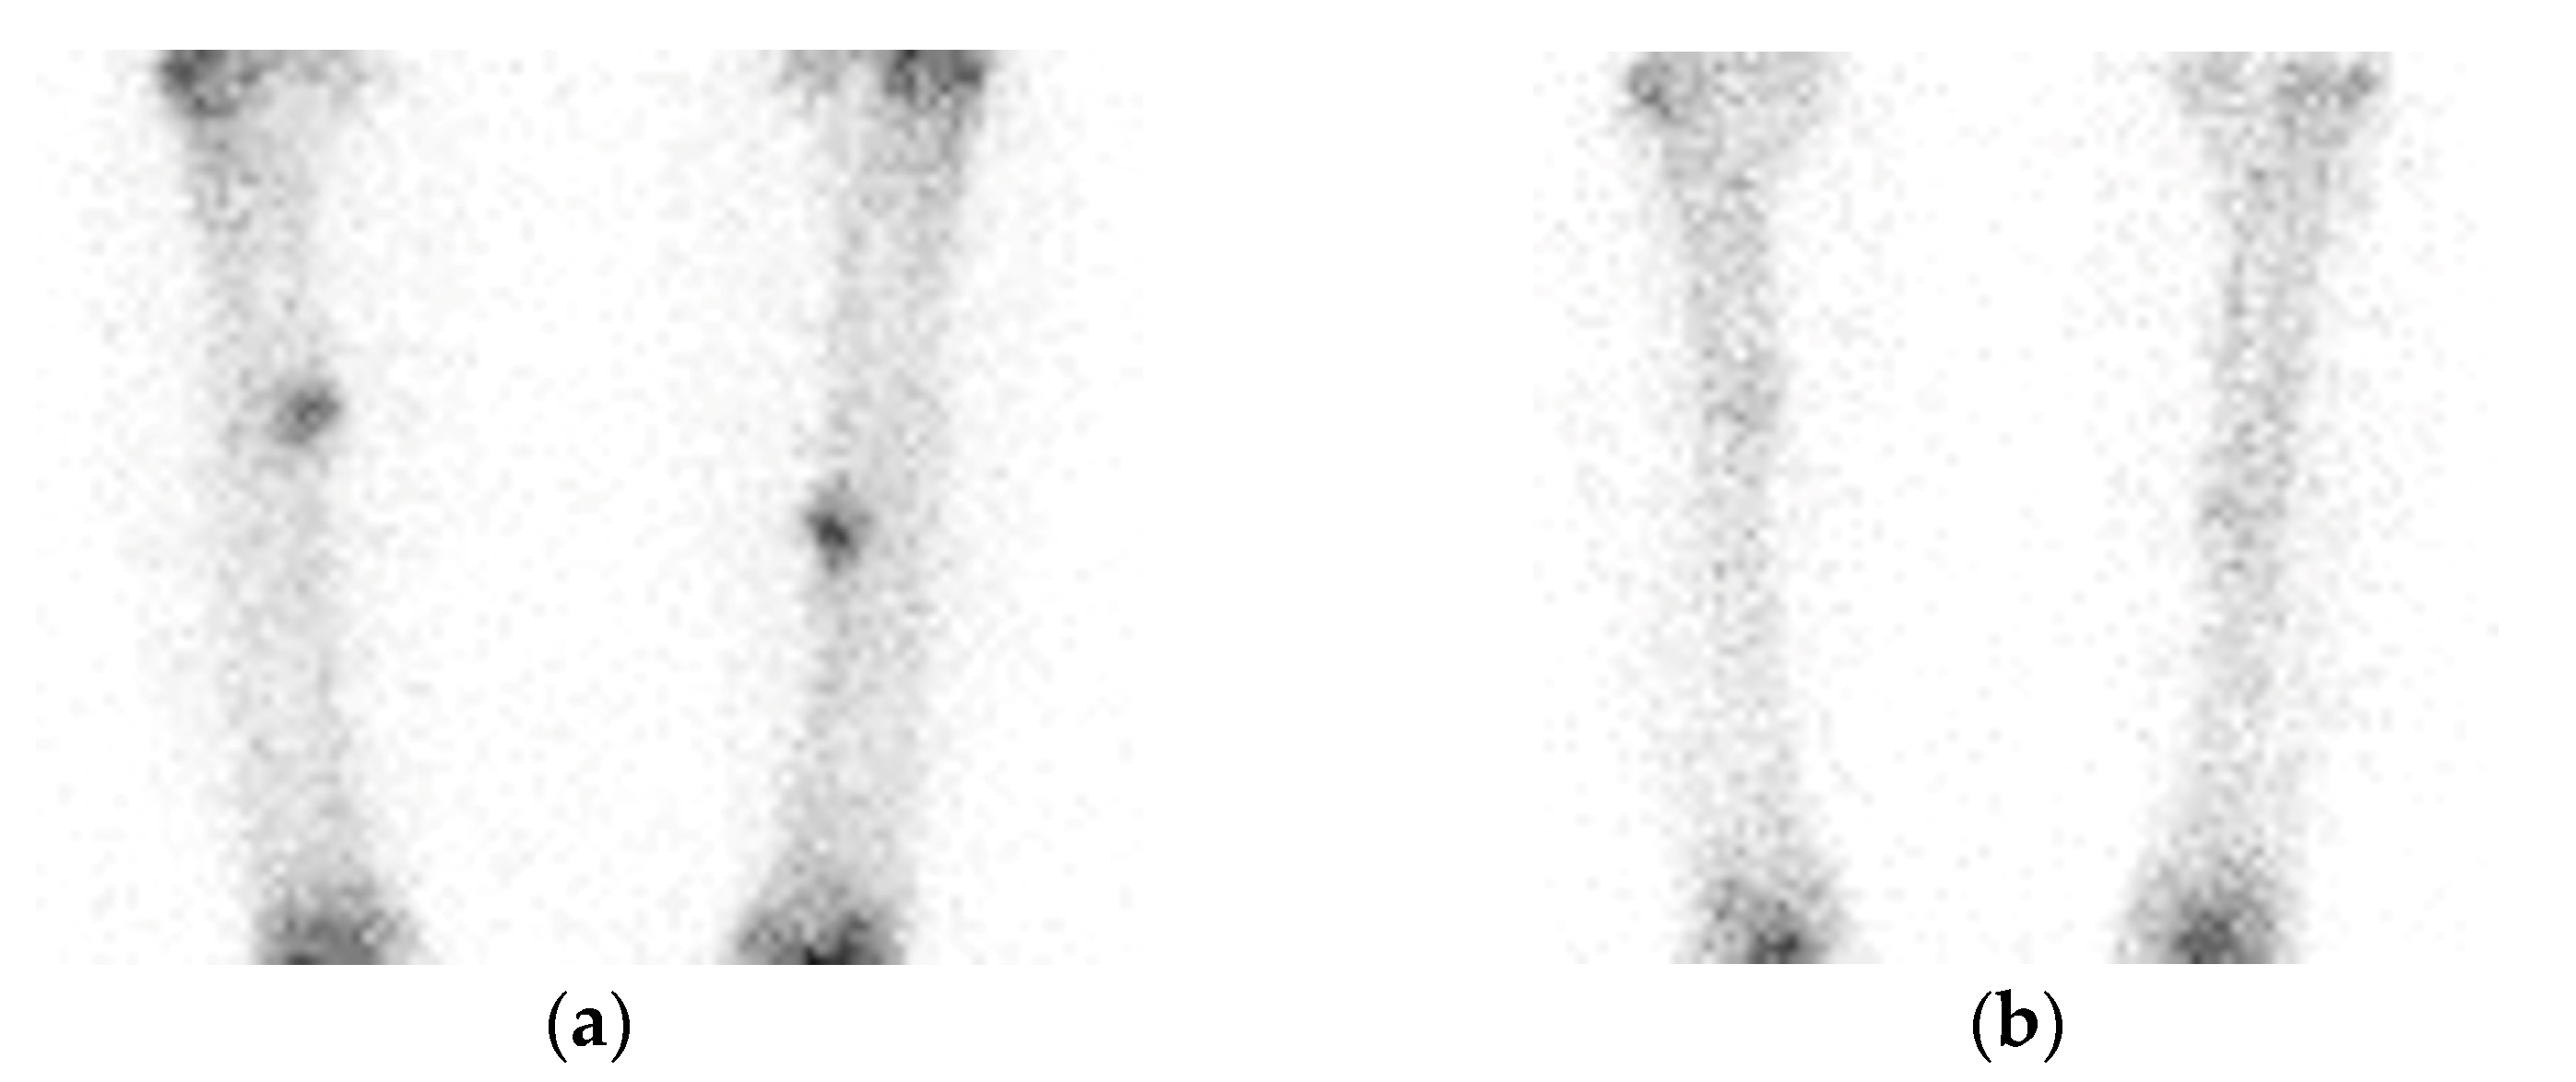

2. Case Presentation

2.1. Patient 1

2.2. Patient 2

2.3. Patient 3